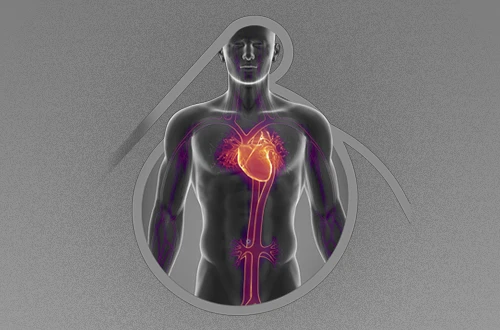

O que são doenças arteriais?

As artérias são os vasos sanguíneos responsáveis por levar o sangue rico em oxigênio e nutrientes do coração para todo o corpo. As doenças arteriais, portanto, são condições que afetam a estrutura ou o funcionamento dessas artérias.

Quando as artérias são afetadas, o fluxo sanguíneo pode ser comprometido, o que pode levar a problemas graves se não forem diagnosticados e tratados a tempo.

Os tipos mais comuns de doenças arteriais

Na minha prática, lido com diversos tipos de doenças arteriais, e o acompanhamento e a avaliação preventiva de cada uma são cruciais. Os tipos mais comuns incluem:

Aneurismas

Um aneurisma é uma dilatação anormal em uma artéria, que pode se romper e causar sangramento grave.

Doença Arterial Periférica

Esta condição se caracteriza pelo estreitamento ou bloqueio das artérias que levam sangue para as pernas e pés. Pacientes com essa doença podem sentir dor ao caminhar, ter pés frios, feridas que não cicatrizam ou dormência.

Doença Carotídea

A doença carotídea é o estreitamento das artérias carótidas, localizadas no pescoço, que fornecem sangue ao cérebro. Essa condição é perigosa porque pode levar a um AVC (Acidente Vascular Cerebral).

Você já fez um check-up da sua circulação?

A avaliação preventiva da circulação é fundamental para identificar riscos, como os de um AVC, e garantir que seu sistema circulatório esteja funcionando corretamente.